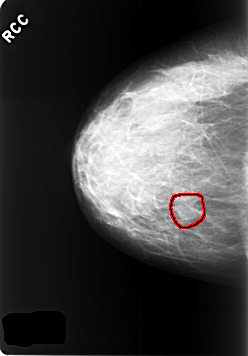

C_0421_1.RIGHT_CC

RIGHT_CC LINES 5688 PIXELS_PER_LINE 3968 BITS_PER_PIXEL 12 RESOLUTION 50 OVERLAY

FILE: C_0421_1.RIGHT_CC.OVERLAY

TOTAL_ABNORMALITIES 1

ABNORMALITY 1

LESION_TYPE MASS SHAPE LOBULATED MARGINS OBSCURED

ASSESSMENT 3

SUBTLETY 4

PATHOLOGY BENIGN_WITHOUT_CALLBACK

TOTAL_OUTLINES 1

BOUNDARY